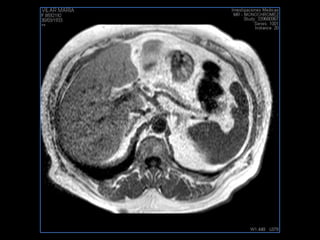

PROTOCOLO abdomen COR T2, AXIAL supresion grasa AX T1 +SAG T2  CON   GADOLINIO :  COR T1+AX T1(DIN) SAT: NO  FASE: RL THK: 6MM  COIL:  GAP: (FACTOR 1.4) 2MM FOV: 40 CM NEX:2 SINCRONIZACION RESPIRATORIA EN 3 O 4 CICLOS ALE